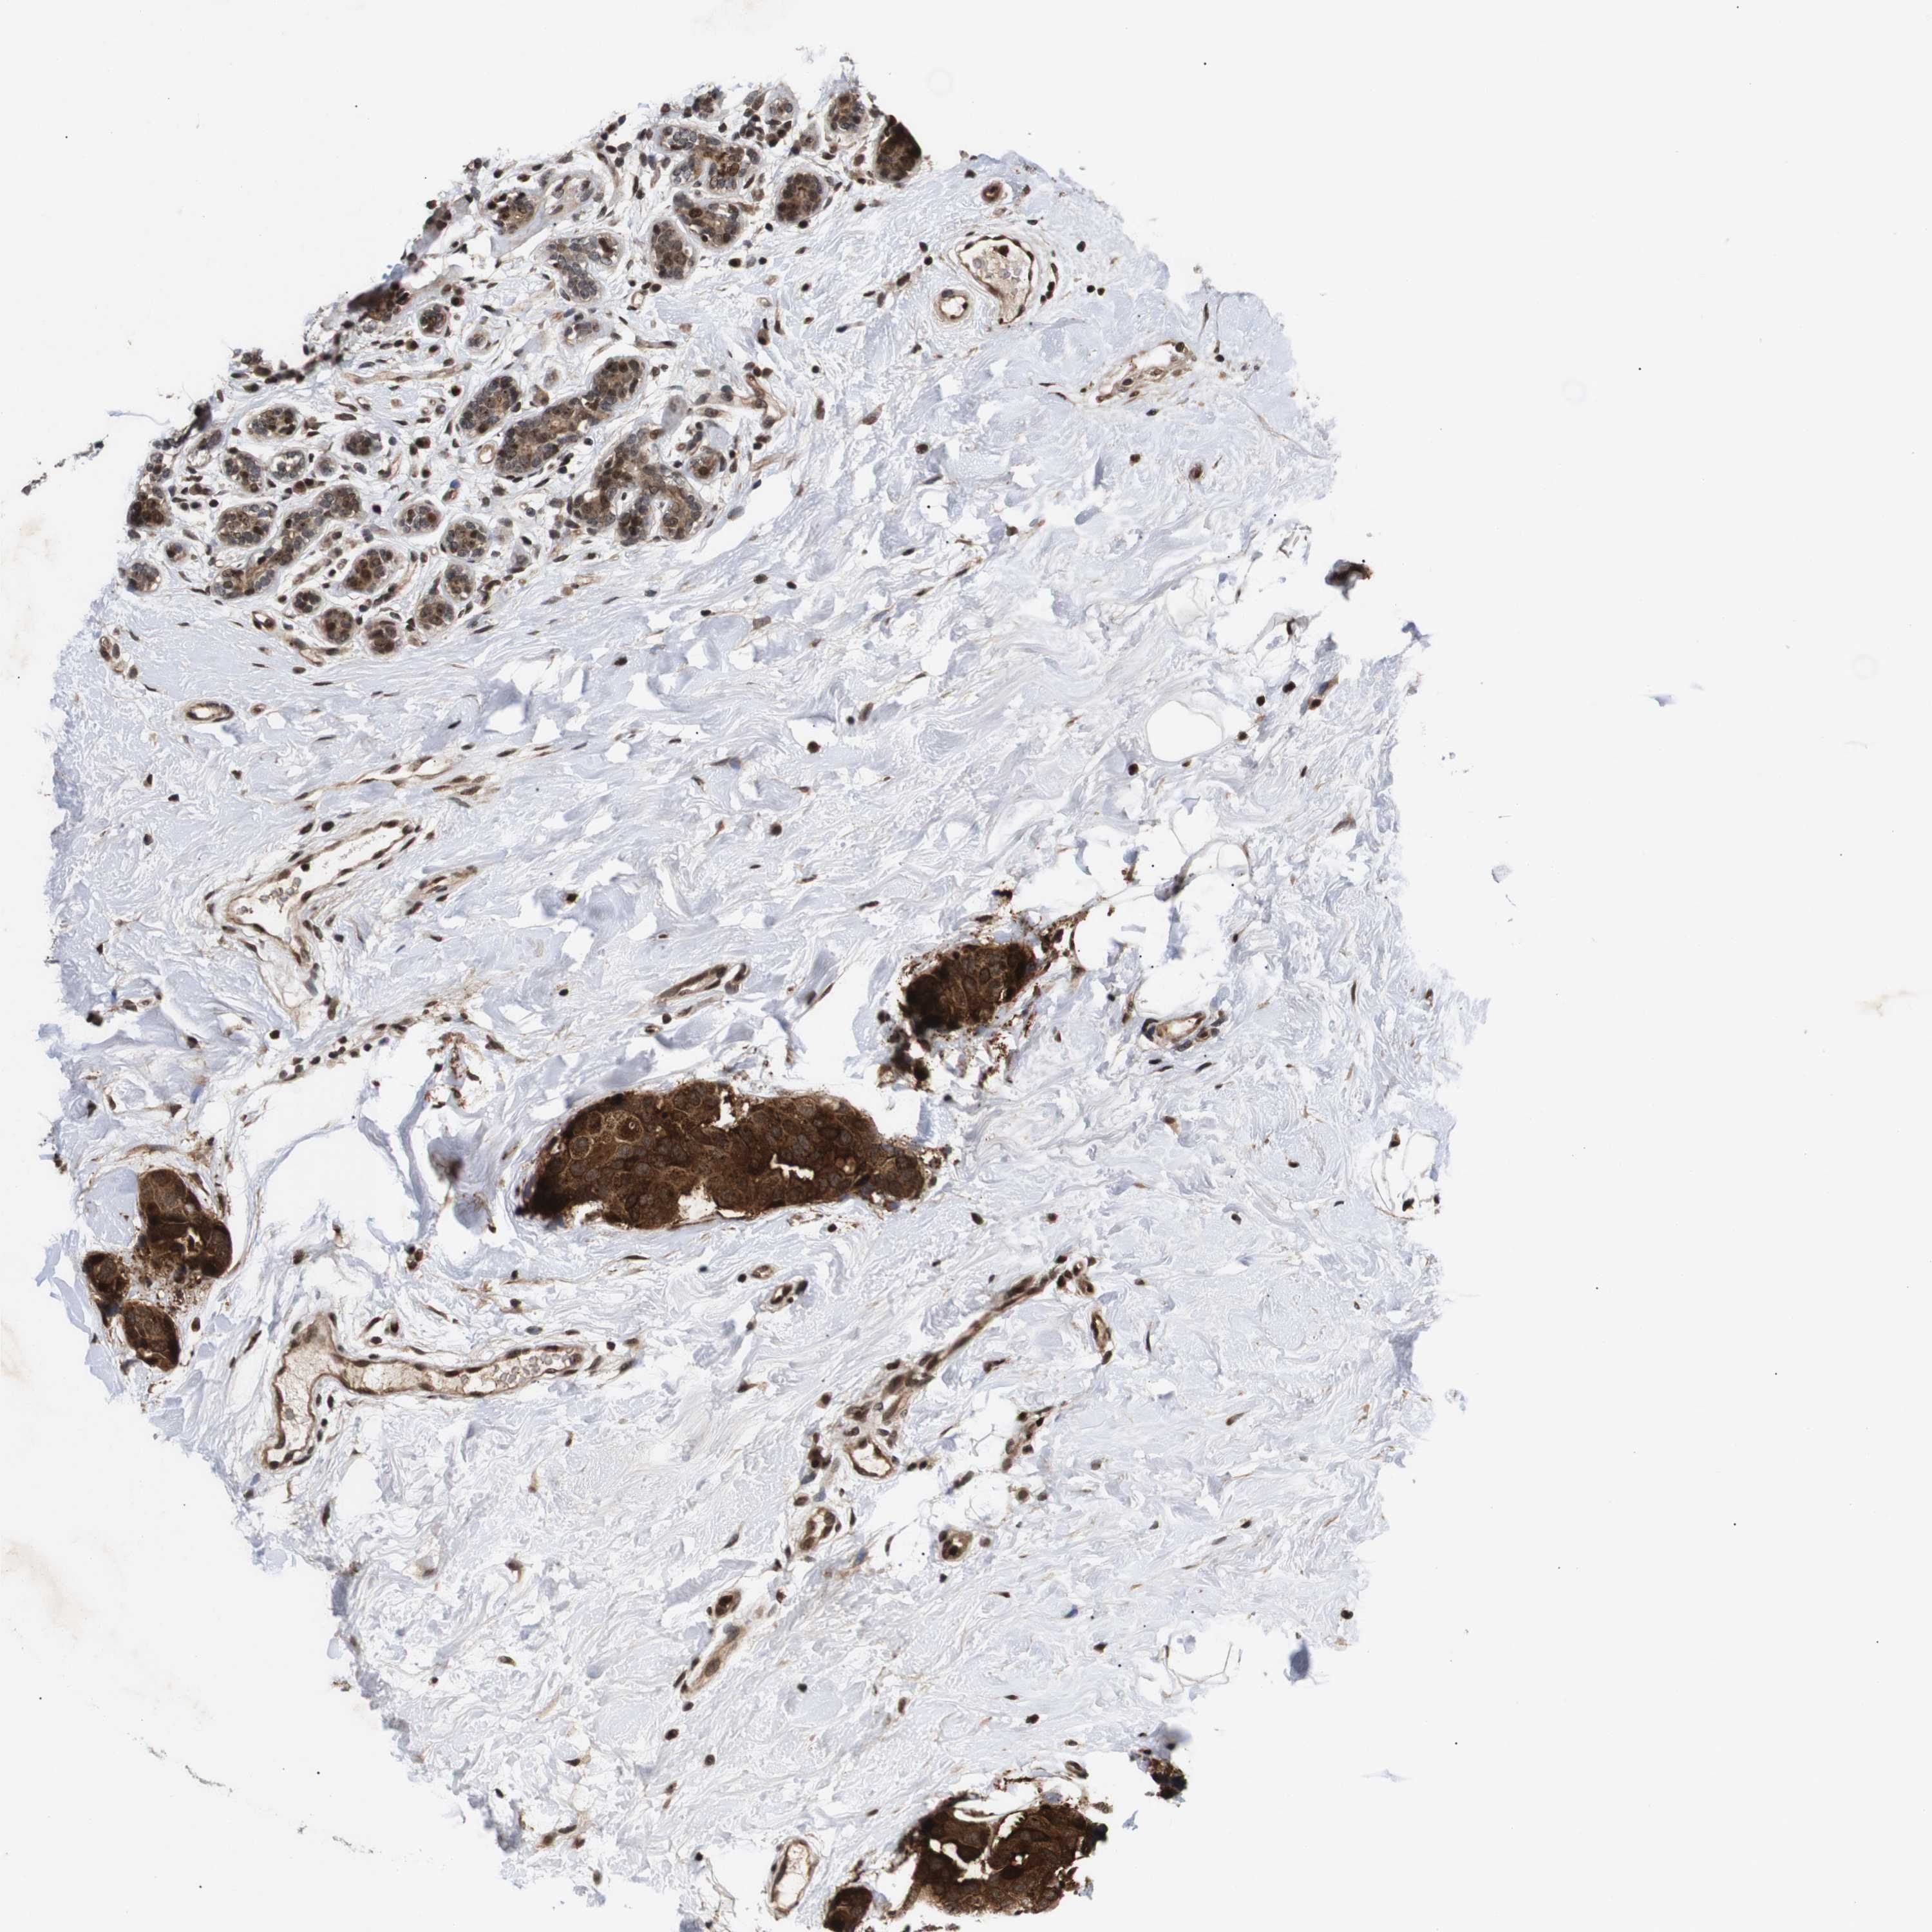

BRCA TCGA BRCA VALIDATION PROTEIN EXPRESSION

ANTIBODIES

AND

VALIDATION